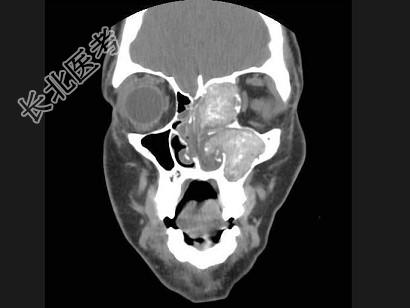

- 多项选择题男,17岁, 左侧上睑下垂,CT检查如图所示, 正确的描述或诊断是 ( )

A、左侧上颌窦、筛窦内见软组织密度影

B、左侧上颌窦窦口扩大

C、鼻中隔、左侧眶内壁、上颌窦内侧壁骨质破坏

D、霉菌性副鼻窦炎

E、细菌性副鼻窦炎